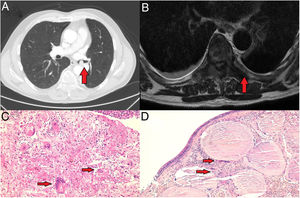

A 60-year-old male patient under study for loss of muscle strength in the lower limbs and advanced asthenia with the presence of hypoaesthesia of the L5 territory of the right lower limb. Computed axial tomography and magnetic resonance imaging requested as a complementary study revealed the presence of a 10.5mm×11mm endobronchial nodular lesion in the left main bronchus (Fig. 1A), as well as the existence of a pathological fracture in the D11 vertebral body and a hyperinflating lytic lesion in the D7 vertebra, with partial infiltration of its posterior elements and edema of the adjacent prevertebral soft tissues (Fig. 1B).

(A) 10.5mm×11mm endobronchial nodular lesion located in the left main bronchus. (B) Hyperinflating lytic lesion in the D7 vertebra, with partial infiltration of its posterior elements and edema of the adjacent prevertebral soft tissues. (C) Soft tissue biopsy (×20): multinucleated giant cells (red arrows) loosely distributed along with numerous mononuclear cells in a fibrous background (×20 magnification). (D) Bronchial mucosa (×10): atypical cell proliferation located at the level of the submucosa composed of soft-looking mononuclear cells, multinucleated giant cells (red arrow) and formation of metaplastic bone tissue (red arrow).

A bone and soft tissue biopsy was performed at location D7 for histological study (Fig. 1C), as well as decompression by arthrodesis D5-L1 and therapeutic rigid bronchoscopy with excision of the excrescent hypervascularized and friable lesion in the distal lateral wall of the left main bronchus, which caused a 60% stenosis of the bronchial lumen undergoing histological study (Fig. 1D) compatible with giant cell tumor metastasis of bone tissue. The patient received treatment with denosumab, with good tolerance, achieving tumor stability and absence of endobronchial recurrence and spinal radiotherapy (D7–8 and D11) of 20Gy in 5 sessions with good tolerance and clinical improvement.